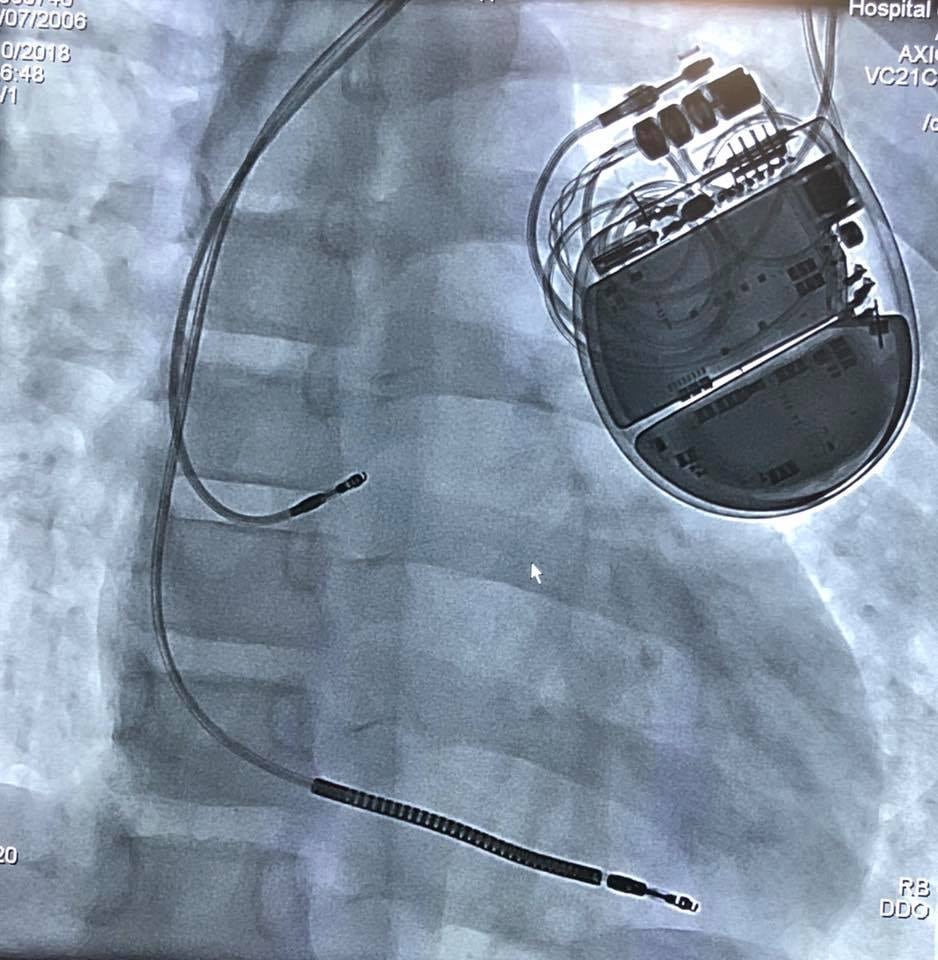

La solución no podía hacerse esperar. Cuando el menor estuvo estable y bajo control, con latidos del corazón constantes, fue trasladado en ambulancia hasta el HNN, donde ya sabían los pasos por seguir: la colocación de un dispositivo llamado implante desfibrilador automático, que es capaz de “leer” cuando el menor tiene un ritmo irregular en el corazón y envía descargas eléctricas hasta regularlo.

Este implante nunca había sido colocado en el país, dado que son pacientes sumamente específicos los que pueden necesitarlo.

La parte más difícil del procedimiento no es la colocación del implante, pues este se coloca de manera muy similar a como se hace con un marcapasos. Lo realmente trascendental es programar el aparato para que sepa cuáles son las condiciones “normales” y a partir de cuáles debe descargar y con qué magnitud.

¿Cómo funciona el dispositivo? Si el corazón del menor no registra un ritmo cardíaco anormal, el aparato está “leyendo” las características de cómo funciona normalmente el corazón, guarda los ritmos y monitorea. Si registra que hay cambios irregulares, envía descargas eléctricas para regular el ritmo. Si no se corrige, está en capacidad de liberar múltiples cargas hasta que se vea corregido.

La vida útil de este aparato es variable y depende de cuántas veces y con cuánta intensidad se produzcan las descargas, pero puede variar de unos cuatro a unos siete años. Después de esto deberá cambiarse.